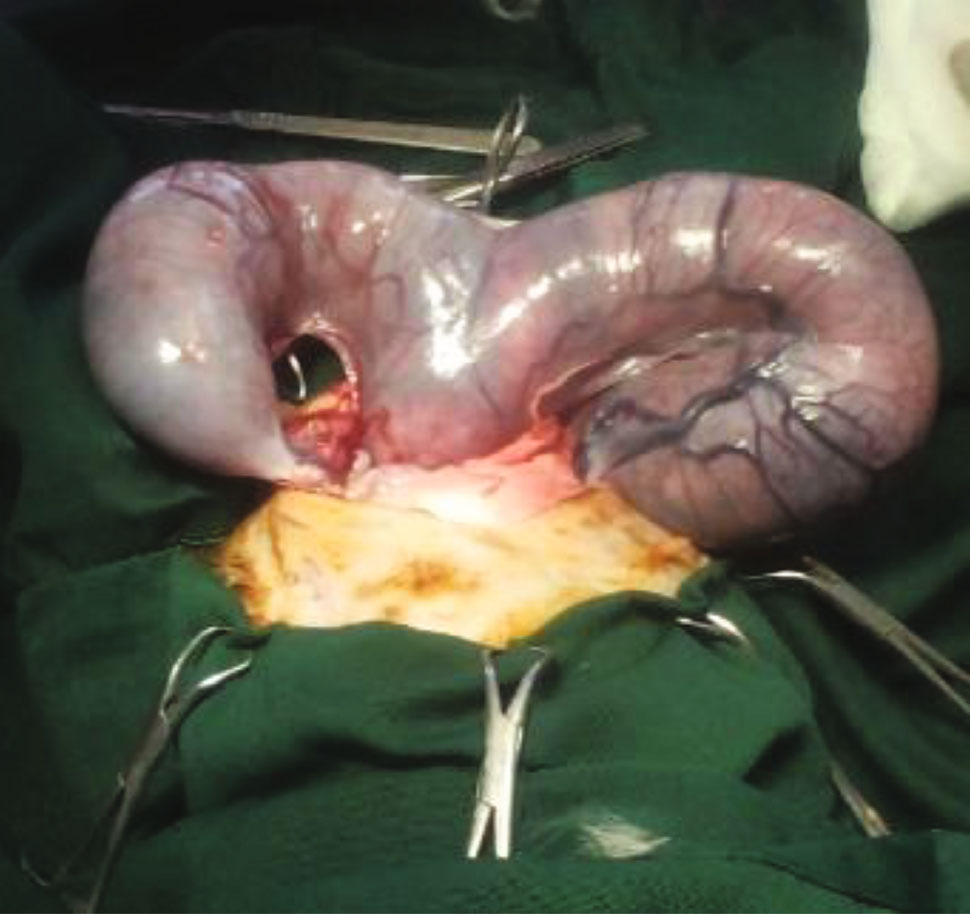

沿左子宫角头侧找到卵巢。锐利地切开悬韧带,夹住卵巢蒂,用双环绕结扎线结扎,横切。在将结扎的残端还纳入腹部之前确认止血。右侧卵巢蒂也同样结扎并横切。在阔韧带上进行开窗,并在横切韧带之前结扎主要血管。

将子宫体拿出,子宫颈触诊留存胎儿。在子宫颈交界处放置环形结扎线,子宫血管单独结扎。将两个夹子放置在结扎线上方(下图),并在它们之间横切子宫。

↑ 两个止血夹放置在子宫体结扎线的头侧。